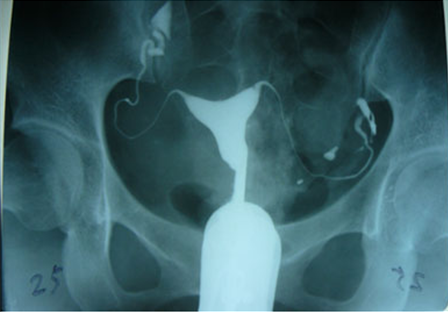

输卵管造影检查,在排除急性及亚急性内外生殖器炎症以及其他禁忌症的情况下,安排在月经干净后3-7天(月经干净后不要同房)检查。